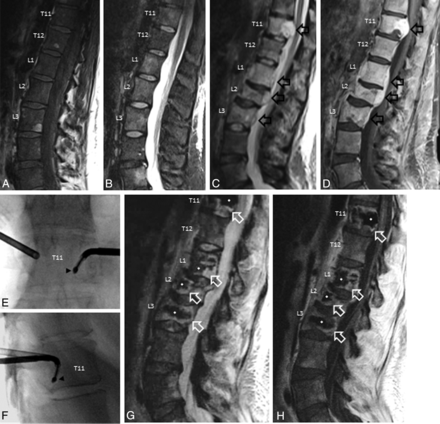

A 29-year-old woman with stage IV (T1b, N1, M1) cardiac angiosarcoma who presented with low back pain. Sagittal T1-weighted (A) and STIR (B) MR imaging show diffuse T1 hypointensity and heterogeneous T2 hyperintensity of the lumbar vertebral body marrow, consistent with marrow-replacing tumor. She was treated with conventional external-beam radiation therapy (30 Gy in 10 fractions); however, her back pain persisted. Sagittal STIR (C) and T1-weighted, fat-suppressed, postcontrast (D) MR imaging performed 5 months later show interval progression of multiple spinal metastases with new epidural extension of tumor at T11, L1, L2, and L3 (black block arrows) and pathologic fractures of the L2 and L3 vertebral bodies. She could not receive additional radiation therapy due to the cumulative dose to the spinal cord. Consequently, she underwent radiofrequency ablation and vertebral augmentation of T11, L1, L2, and L3. Anteroposterior (E) and lateral (F) fluoroscopic images show percutaneous cannulae in both pedicles of T11 and the ablation probe curving into the left posteroinferior vertebral body (black arrowheads). Sagittal STIR (G) and T1-weighted, fat-suppressed, postcontrast (H) MR imaging performed 6 months later show interval retraction of the epidural tumor at T11, L1, L2, and L3. Signal void corresponding to cement (white asterisks) with surrounding T2-hyperintense, enhancing granulation tissue is noted at the treated levels (white block arrows).

In the present study, combination RFA and vertebral augmentation achieved 1-year radiographic local control rates of 70% (21/30) overall and 67% (18/27) in the setting of systemic metastatic disease progression. These results suggest the possibility of a new, multidisciplinary paradigm for managing metastatic spine disease that incorporates RFA and vertebral augmentation for local tumor control.18 Although radiation therapy is the standard of care for palliation and local control of osseous metastatic disease, RFA and vertebral augmentation may be an effective alternative for patients who cannot be offered or cannot tolerate radiation therapy or have radiation-resistant tumors (Fig 1). A prospective clinical trial is now needed to replicate these results.